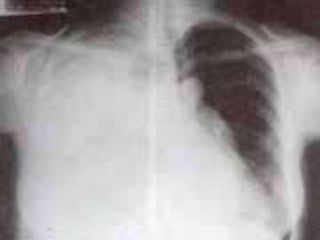

CRITERIOS DE EVALUACIONRX. TX.  Pulmones desde ápex hasta senos costo diafragmáticos  Pulmones y corazón sin rotación.  10 pares de costillas.  Sombra área de la tráquea centrada sobre la columna.  Balance en los contrastes de la imagen (exposición adecuada).

INTERPRETACION  Revisar estructuras óseas.  Partes blandas.  Espacios intercostales.  Parénquima pulmonar  Nivel de los senos costodiafragmaticos.  Neumatización.  Trama alveolo-pulmonar  Silueta cardiaca  Cayado aórtico.